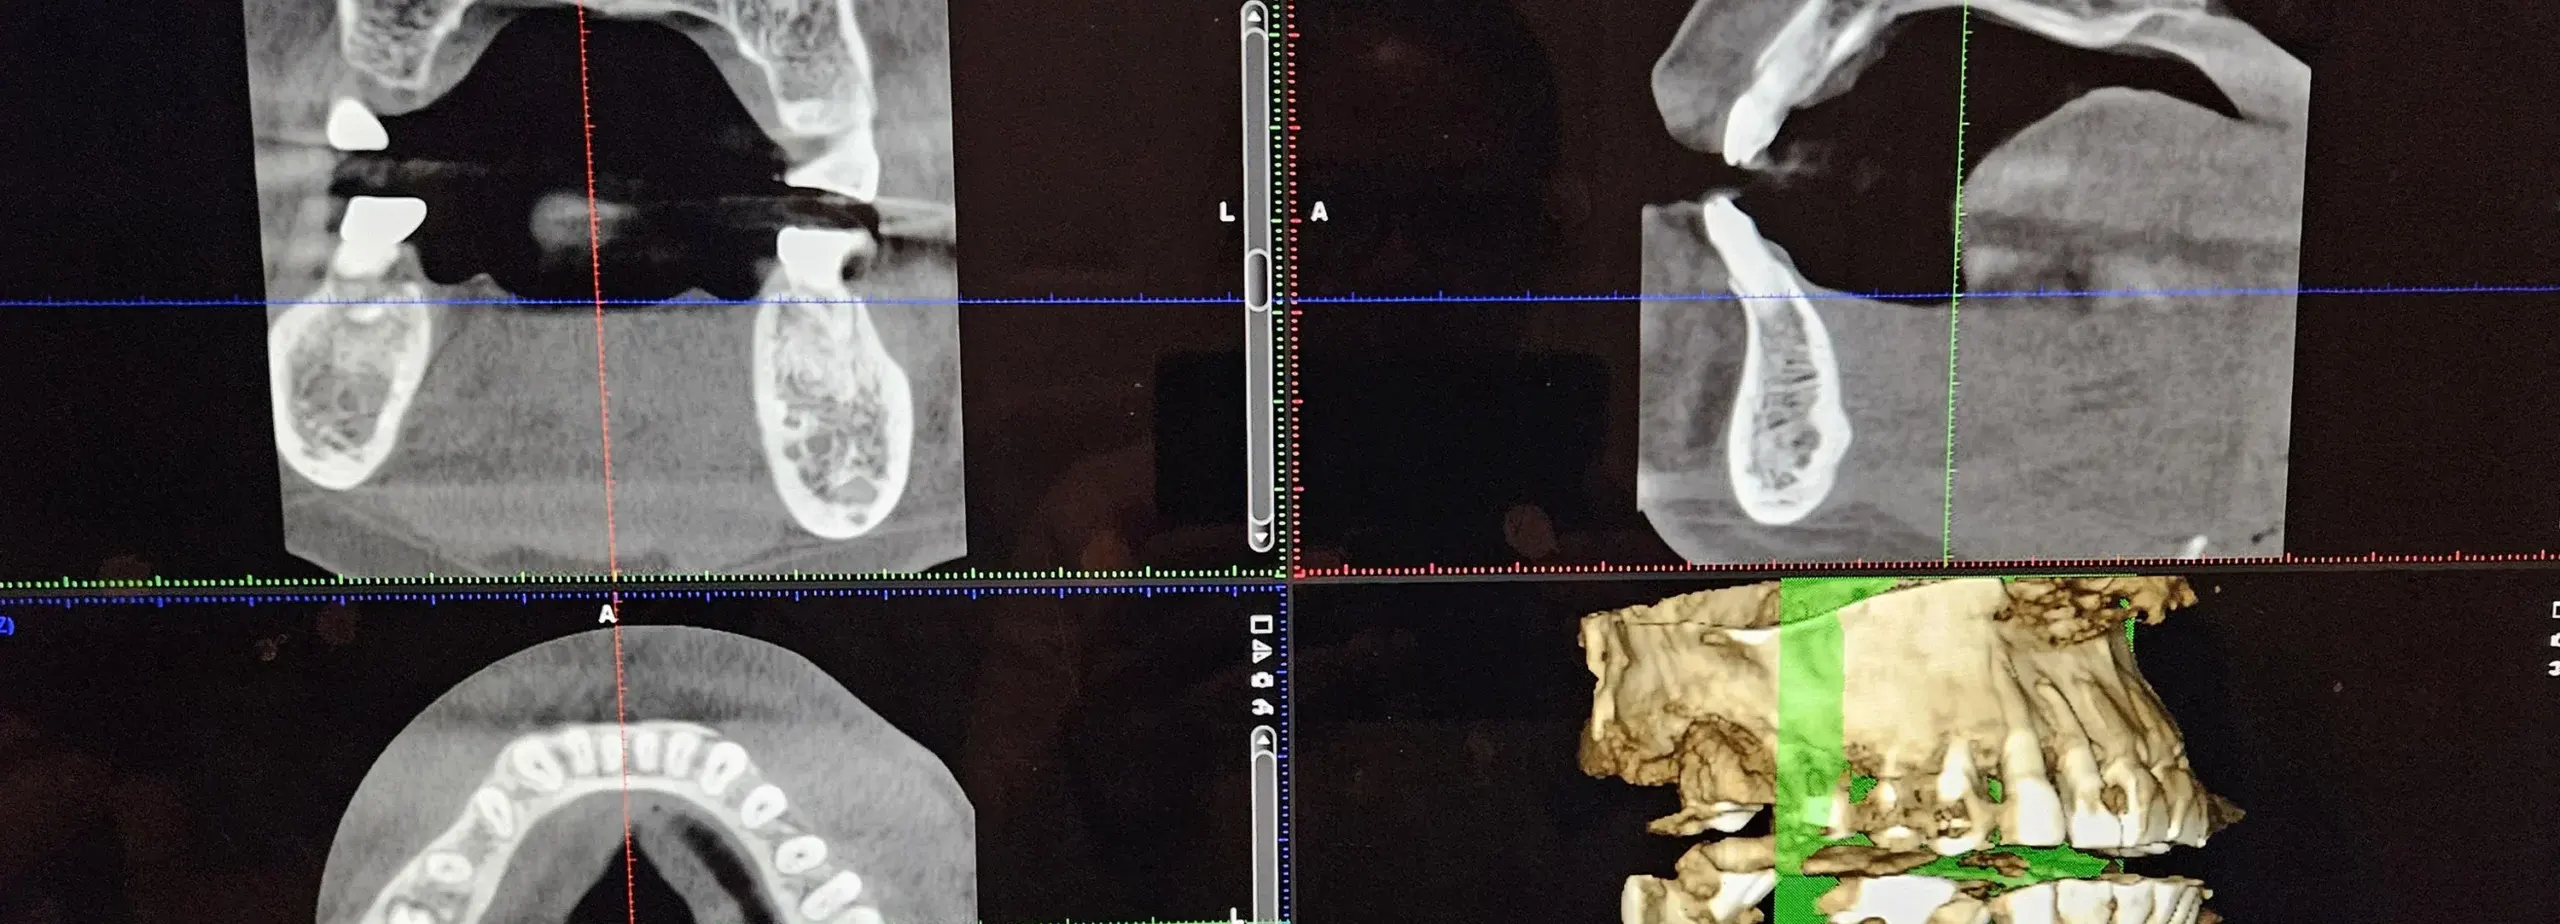

CBCT (Cone-Beam Computed Tomography) is a game-changer in dental technology. This 3D imaging system provides high-resolution images of the teeth, jaws, and surrounding structures, allowing dentists to plan and execute treatments with unparalleled precision. With CBCT, our team can detect and diagnose issues that may not be visible with traditional X-rays.

- Detailed 3D Imaging — CBCT provides three-dimensional images that offer a comprehensive view of the mouth, including the teeth, jawbone, and surrounding tissues. This provides a comprehensive view of the dental structure, enabling detailed analysis and precise treatment planning.

- Highly Accurate & Rapid Results — CBCT scans are quick and provide superior accuracy. The high-resolution images enable us to measure bone density, detect root fractures, and view the smallest details, such as the interior of the tooth, leading to accurate diagnoses and effective treatment plans.